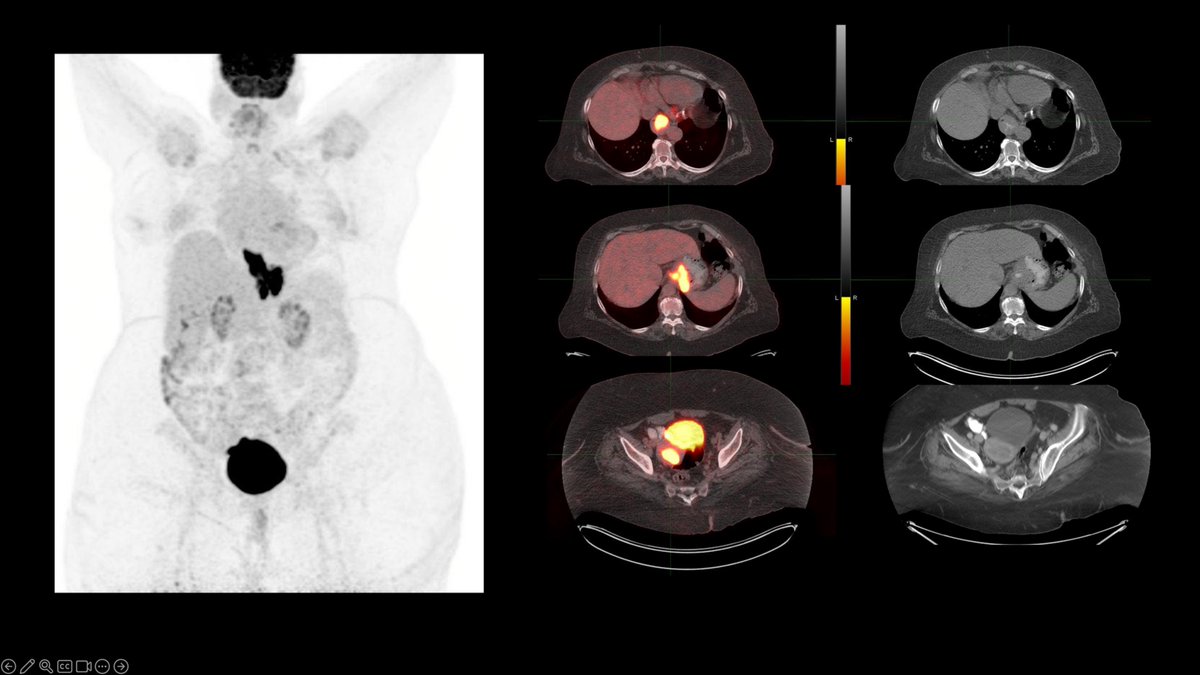

Case Challenge: # 57

Test your skills by providing answers in comments. Come back to check the answer key in 24 -48h.

Get all the cases at: nuclearmd.com/courses